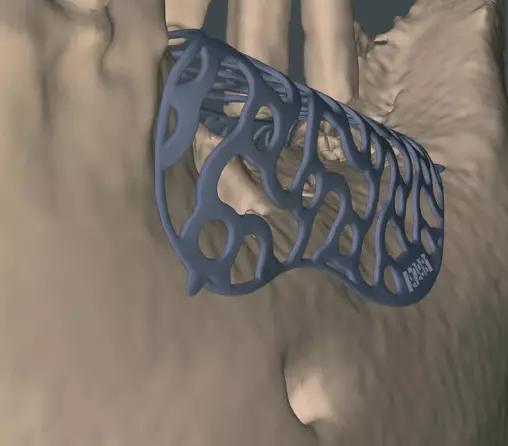

Die „guided surgery“ ist aktuell in aller Munde, ob in der Endodontie, der Implantologie oder eben der augmentativen Chirurgie. Erweitert und verbessert wird diese Methode mit der modernen 3D-Bildgebung, wie einem CT oder DVT, die eine umfangreiche präoperative Planung und damit ein individualisiertes, exakt auf den Patienten zugeschnittenes operatives Vorgehen ermöglicht. Zusätzlich können mögliche Komplikationen vermieden oder gegebene anatomische Verhältnisse bestmöglich genutzt werden. Durch den generierten 3D-Datensatz kann mittels DICOM-Daten und entsprechender Software ein individualisiertes CAD/CAM gefertigtes Titangitter geplant und hergestellt werden. Die Titangitter sind exakt auf den Patienten individualisiert und berücksichtigen alle an den Defekt angrenzenden anatomischen Strukturen. So wird eine zeitaufwendige intraoperative Anpassung des Gitters vermieden [11].

Der zweite Patientenfall beschäftigt sich mit einer Patientin Anfang 60, die sich mit einer verkürzten Zahnreihe bis zum Zahn 34 und dem Wunsch der Versorgung des III. Quadranten zu uns in die Praxis kam (Abb. 17a). Allgemeinanamnestisch besteht ein Diabetes mellitus, Sarkoidose und eine Primärprophylaxe mit ASS 100 mg. Die Zähne im III. Quadranten sind schon vor mehreren Jahren verloren gegangen, was die starke vertikale und horizontale Atrophie des Kieferkamms erklärt (Abb. 17b). Nach ausführlicher Aufklärung über alle Behandlungsmöglichkeiten und entstehende Kosten, entschied sich die Patientin für eine festsitzende Implantatversorgung mit drei Implantaten zum Ersatz der Zähne 45-47. Bei der Planung der Implantate zeigte sich das stark ausgeprägte horizontale und vertikale Knochendefizit, was den Knochenaufbau mit einem individuell geplanten Titangitter (Yxoss, ReOss) notwendig machte. Mittels DVT-Daten und entsprechender Planungssoftware wurde das 3D-Gitter individuell, entsprechend der anatomischen Verhältnisse und des benötigten Knochenvolumens, geplant und angefertigt (Abb. 17 c-e).